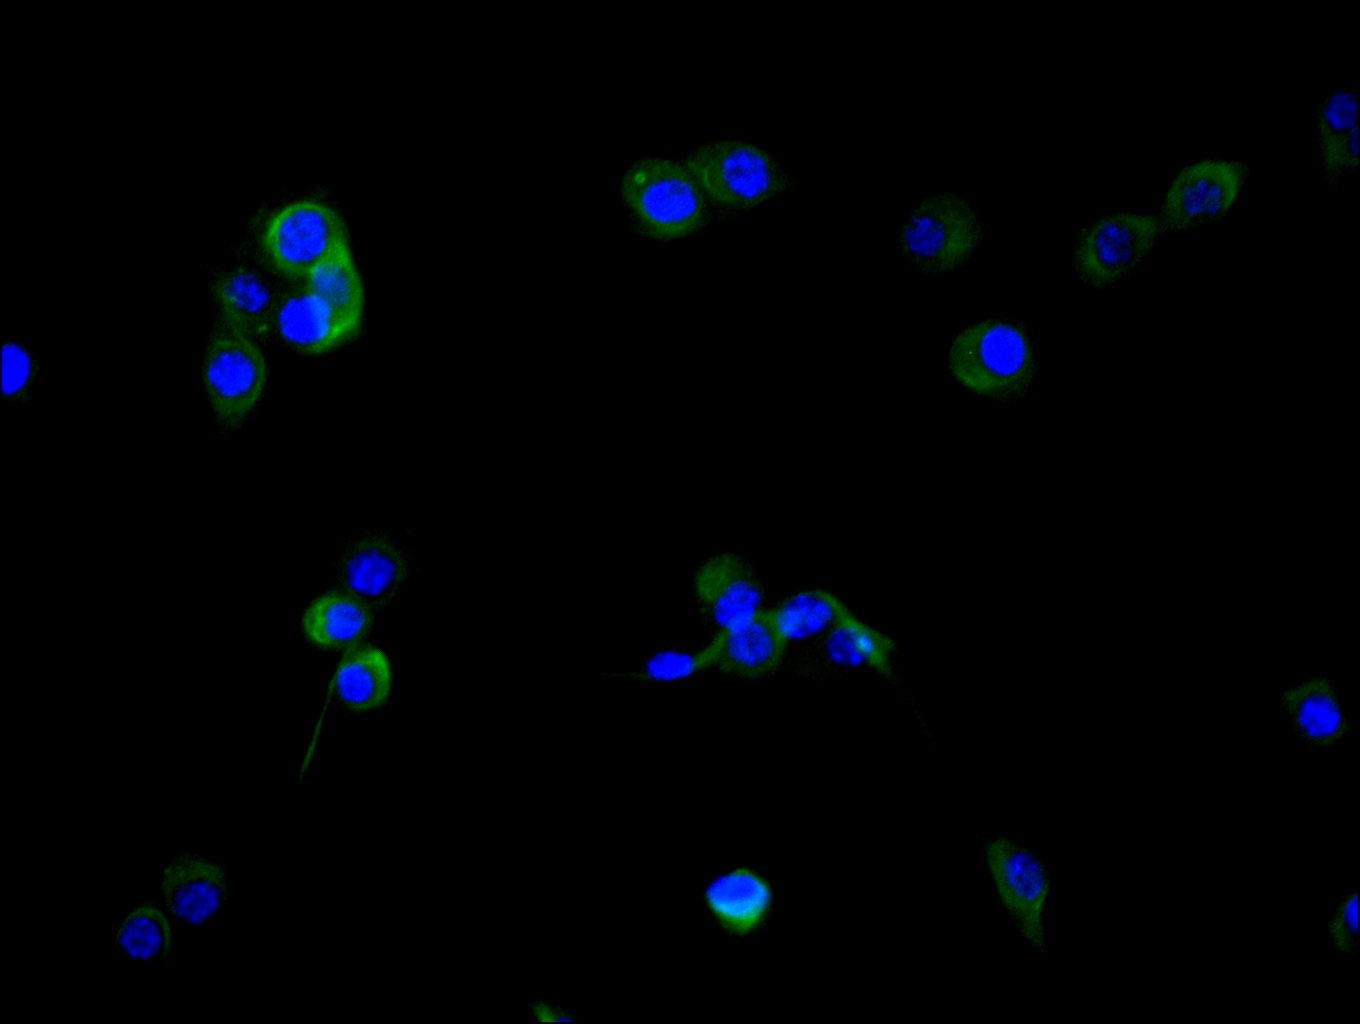

FAP的表达模式使其成为潜在的生物标志物和治疗靶点。研究表明,FAP在超过90%的癌症类型(如乳腺癌、胰腺癌、食管癌和肺癌)中的癌症相关成纤维细胞(CAFs)上高度表达,而在健康成人组织中几乎不表达 [2][3][5][6]。这种病理特异性表达赋予了FAP作为癌症诊断和治疗靶点的巨大潜力 [6]。

FAP作为肿瘤微环境中的关键靶点,其在肿瘤的侵袭、转移、免疫逃逸以及耐药性中发挥重要作用。华美生物提供FAP重组蛋白、抗体及ELISA试剂盒产品,助力您开发特异性靶向FAP的药物,探索其在肿瘤治疗中的应用潜力。

● FAP抗体

FAP Recombinant Monoclonal Antibody; CSB-RA008424MA1HU

FAP Recombinant Monoclonal Antibody; CSB-RA008424MA2HU